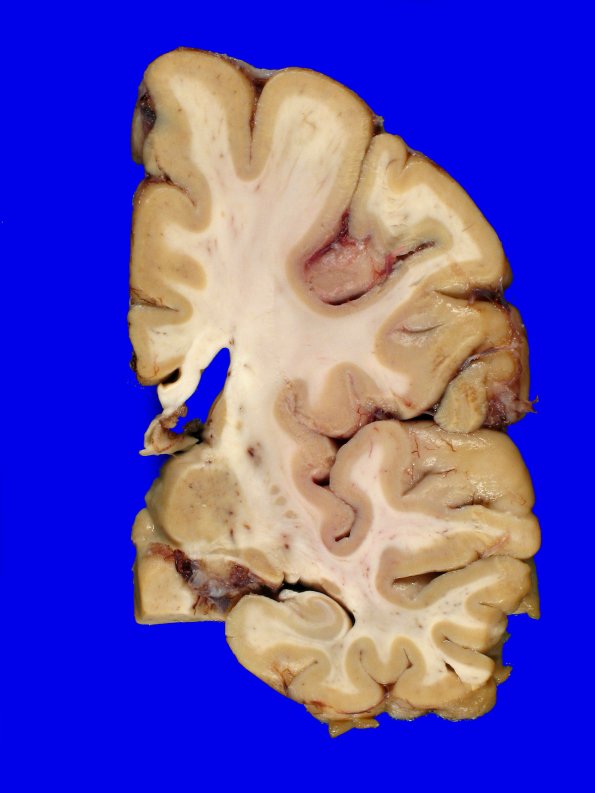

Washington University Experience | METABOLIC | Neuronal Ceroid Lipofuscinosis (NCL) | 10B1 NCL (Case 10) Gross_19

10B1-3 At autopsy, the fresh brain weighed 1,050 g. There was mild generalized atrophy of the cerebral hemispheres and mild dilatation of the lateral ventricles.